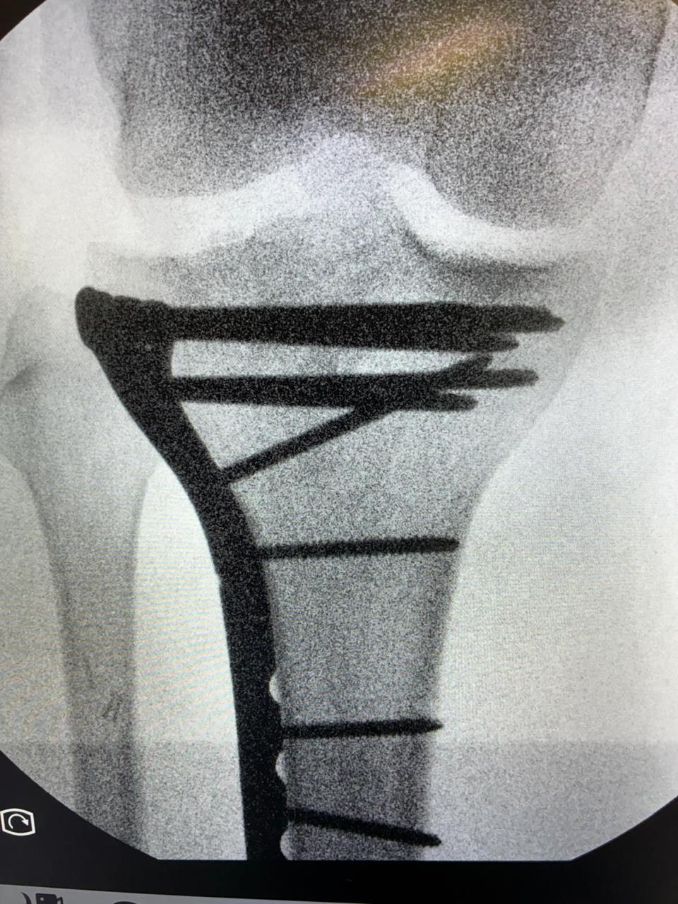

La operación, realizada por el doctor Ruano y su equipo médico, permitió estabilizar el fragmento óseo afectado, además de reparar y fijar varios ligamentos dañados a consecuencia de la violenta cogida. Según el parte facilitado tras la intervención, la cirugía se desarrolló con normalidad y la evolución del torero es favorable en estas primeras horas del postoperatorio.